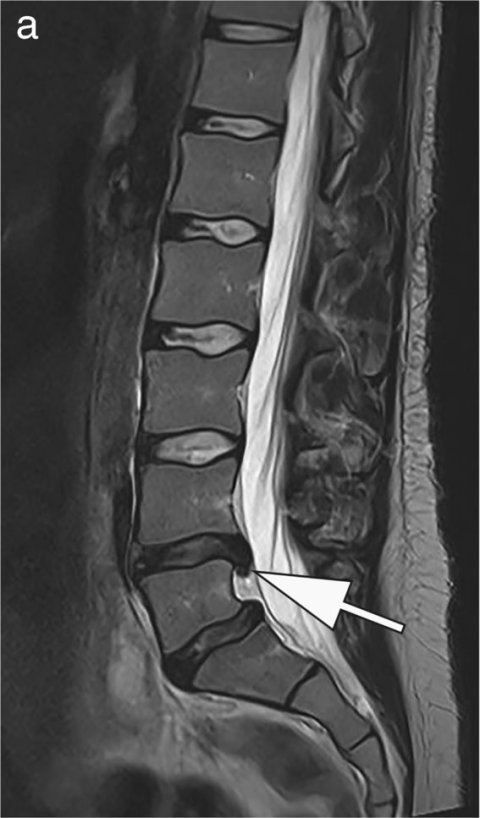

Image source: Pogarell T, Heiss R, Janka R, Nagel AM, Uder M, Roemer FW, Skeletal Radiology 2024 (CC BY 4.0)

Vilanova, who will chair the ESMRMB 2026 meeting, has made low-field implementation a cornerstone of his clinical strategy. In Marseille, he laid out a detailed case for its integration into routine practice: economic sustainability, sufficient diagnostic quality for MSK and spine imaging, and growing support from AI technologies.

‘In my clinic, nearly 80% of MRI requests are for spine or MSK,’ he explained. ‘The question is not whether we can produce beautiful images – the question is whether we can answer the clinical question.’

For knee pain, lumbar discomfort or degenerative joint changes, low-field MRI offers enough diagnostic clarity at a fraction of the cost of high-field scans. ‘We’re not talking about advanced cardiac or prostate imaging,’ he added. ‘We’re talking about the everyday core of radiology, where efficiency matters most.’